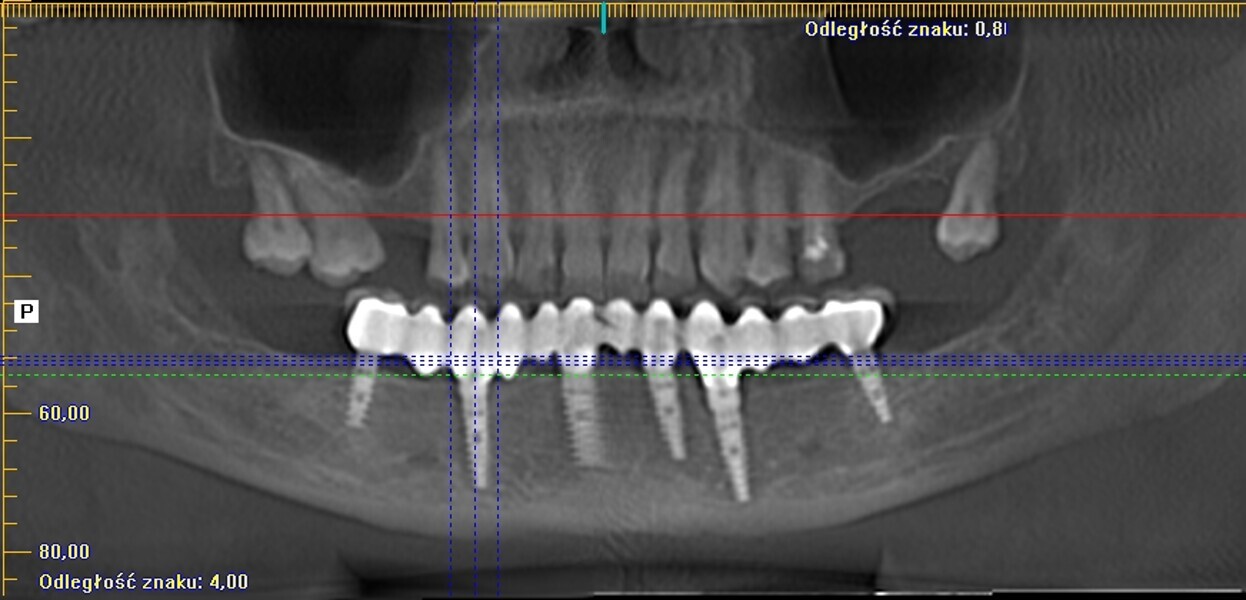

Natychmiastowa implantacja i zaopatrzenie protetyczne pacjentów z zaawansowaną chorobą przyzębia